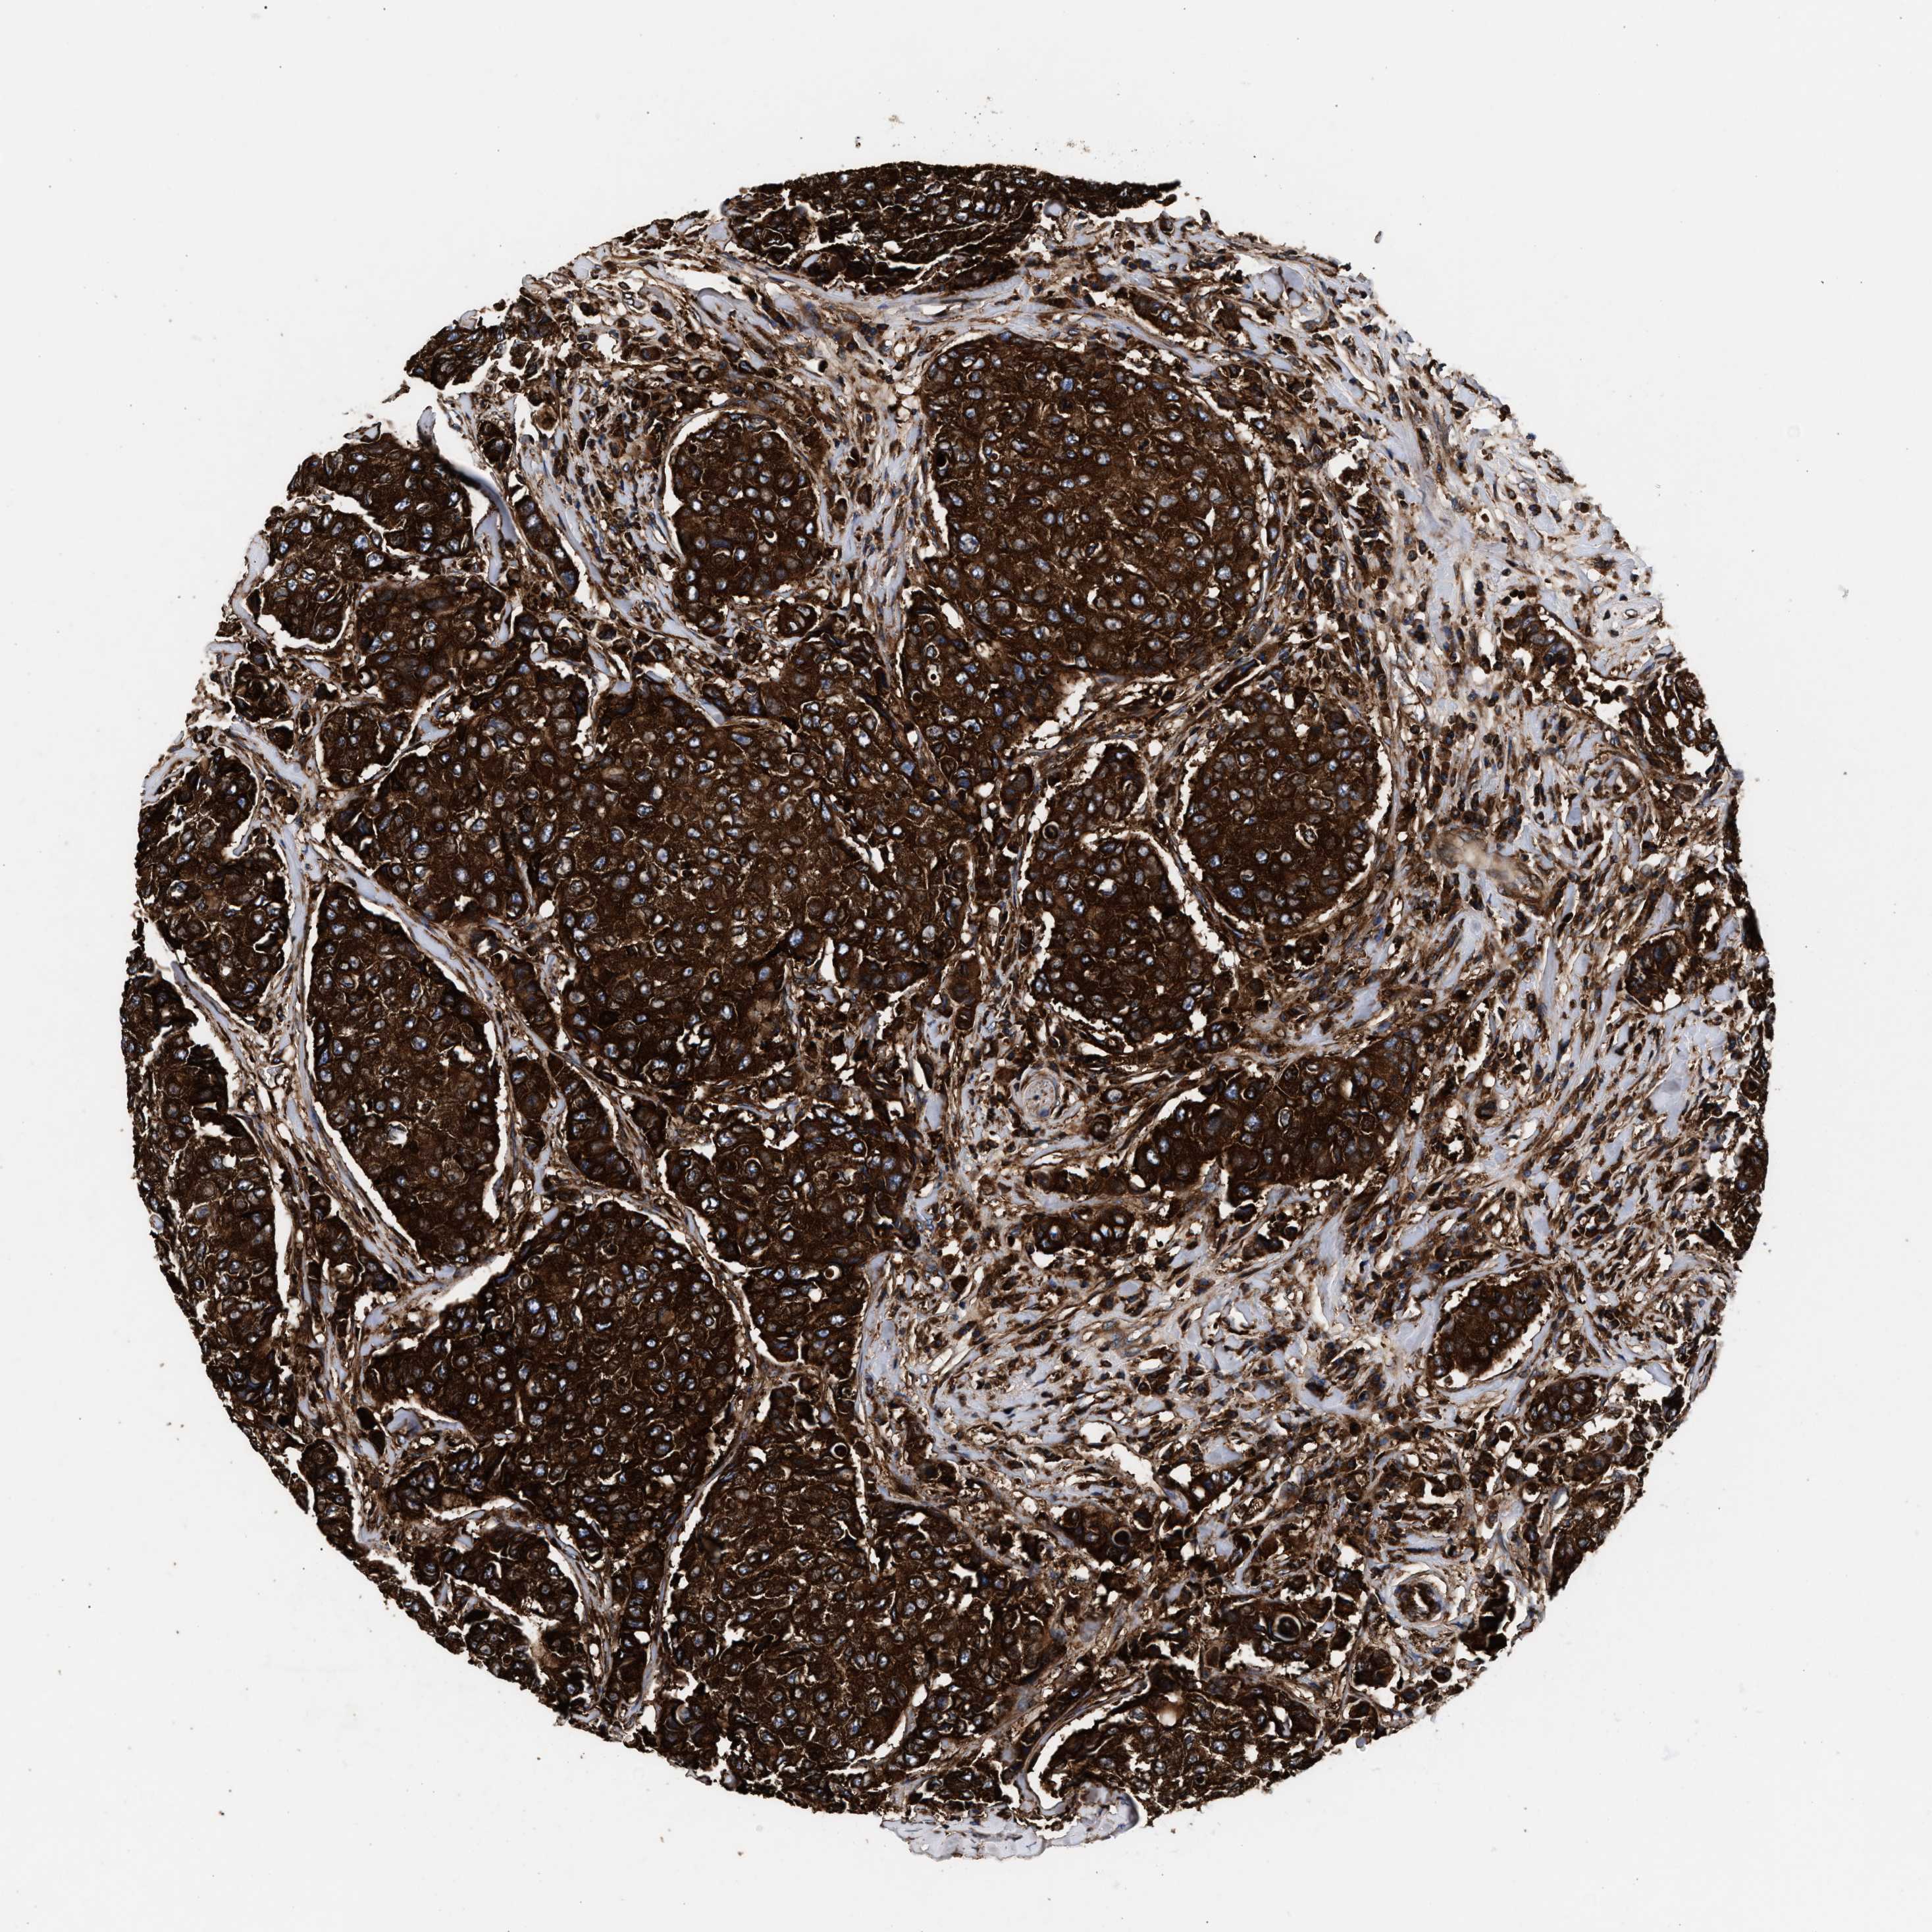

BRCA TCGA BRCA VALIDATION PROTEIN EXPRESSION

ANTIBODIES

AND

VALIDATION